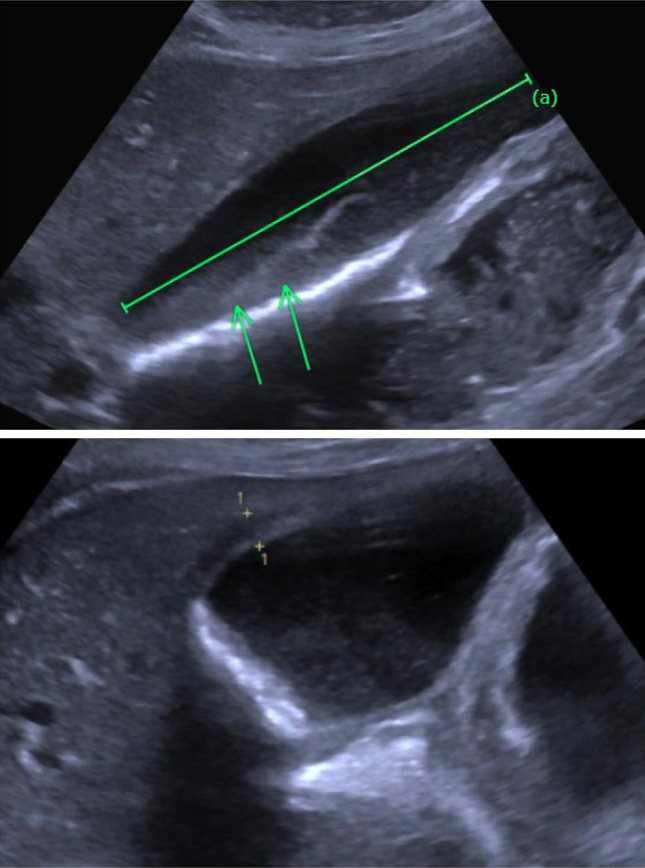

Acalculous cholecystitis (AC) is an inflammatory condition of the gallbladder without the presence of gallstones. Although far less common than calculus cholecystitis, AC is associated with a mortality rate 10 times higher than that of calculus cholecystitis. While normally due to bacterial pathogens, opportunistic ones such as the fungi Candida species (spp) can be rare causative agents of AC, typically observed in those with underlying malignancy or immunosuppression. In this study, we present an unusual case of an immunocompetent patient who was afflicted by fluconazole-resistant Candida glabrata AC. Our case highlights the complexity of this diagnosis and the challenges providers may encounter while treating the underlying infection.